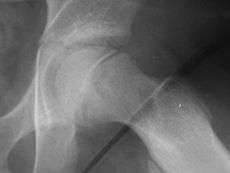

| X-ray showing a slipped capital femoral epiphysis, before and after surgical fixation. | |

The diagnosis requires x-rays of the pelvis, with anteriorposterior (AP) and frog-leg lateral views.[7] The appearance of the head of the femur in relation to the shaft likens that of a "melting ice cream cone", visible with Klein's line. The severity of the disease can be measured using the Southwick angle.